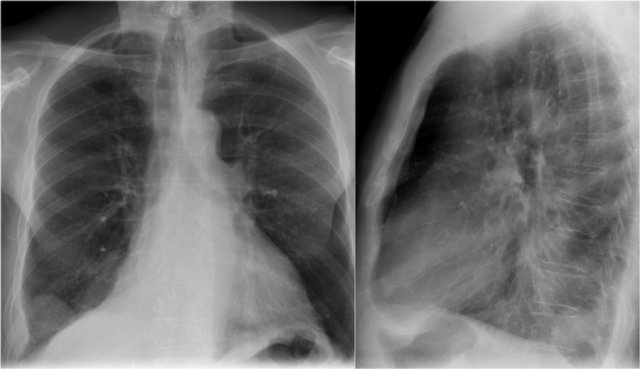

Here a consolidation which is located in the left lower lobe (yellow arrow).

Notice that there is a normal silhouette of the left heart border (blue arrow).

The absence of a silhouette sign tells us that the pathology is located in the left lower lobe and not in the lingula.

Silhouette sign (4)

On this lateral film there is too much density over the lower part of the spine.

First study the lateral film and decide on which side the pathology is located.

Then click on the image to enlarge and scroll through the images.

By only looking at the interfaces of the left and right diaphragm on the lateral film, it is possible to tell on which side the pathology is located.

In this case we cannot follow the contour of the right diaphragm all the way to posterior, which indicates that there is something of water-density in the right lower lobe.

Continue with the PA-film of the same patient...

On the PA-film there is a normal silhouette of the right heart border, so the pathology is not in the anterior part of the chest, which we already had decided by studying the lateral view.

Question:

Why do we still see the silhouette of the right diaphragm on the PA-film?

Answer:

What we see is actually the highest point of the right diaphragm, which is anterior to the pneumonia in the right lower lobe.

The pneumonia does not border the highest point of the right diaphragm and there will be no silhouette sign.